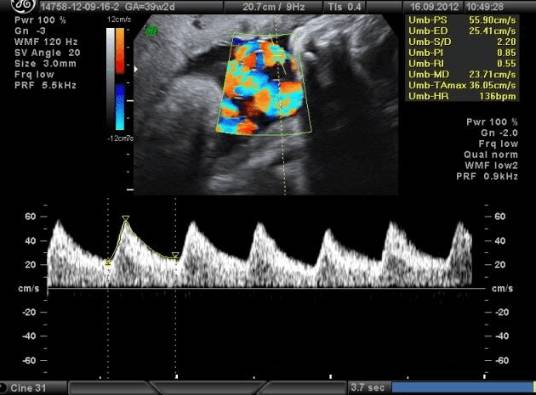

- Допплерография — позволяет оценить состояние кровотока между плацентой и плодом по гемодинамике в артериях пуповины, аорте плода, маточных артериях.

- Кардиотокография (КТГ) – регистрация изменений частоты сердцебиения в ответ на сокращение матки, внешние раздражители, активность плода.